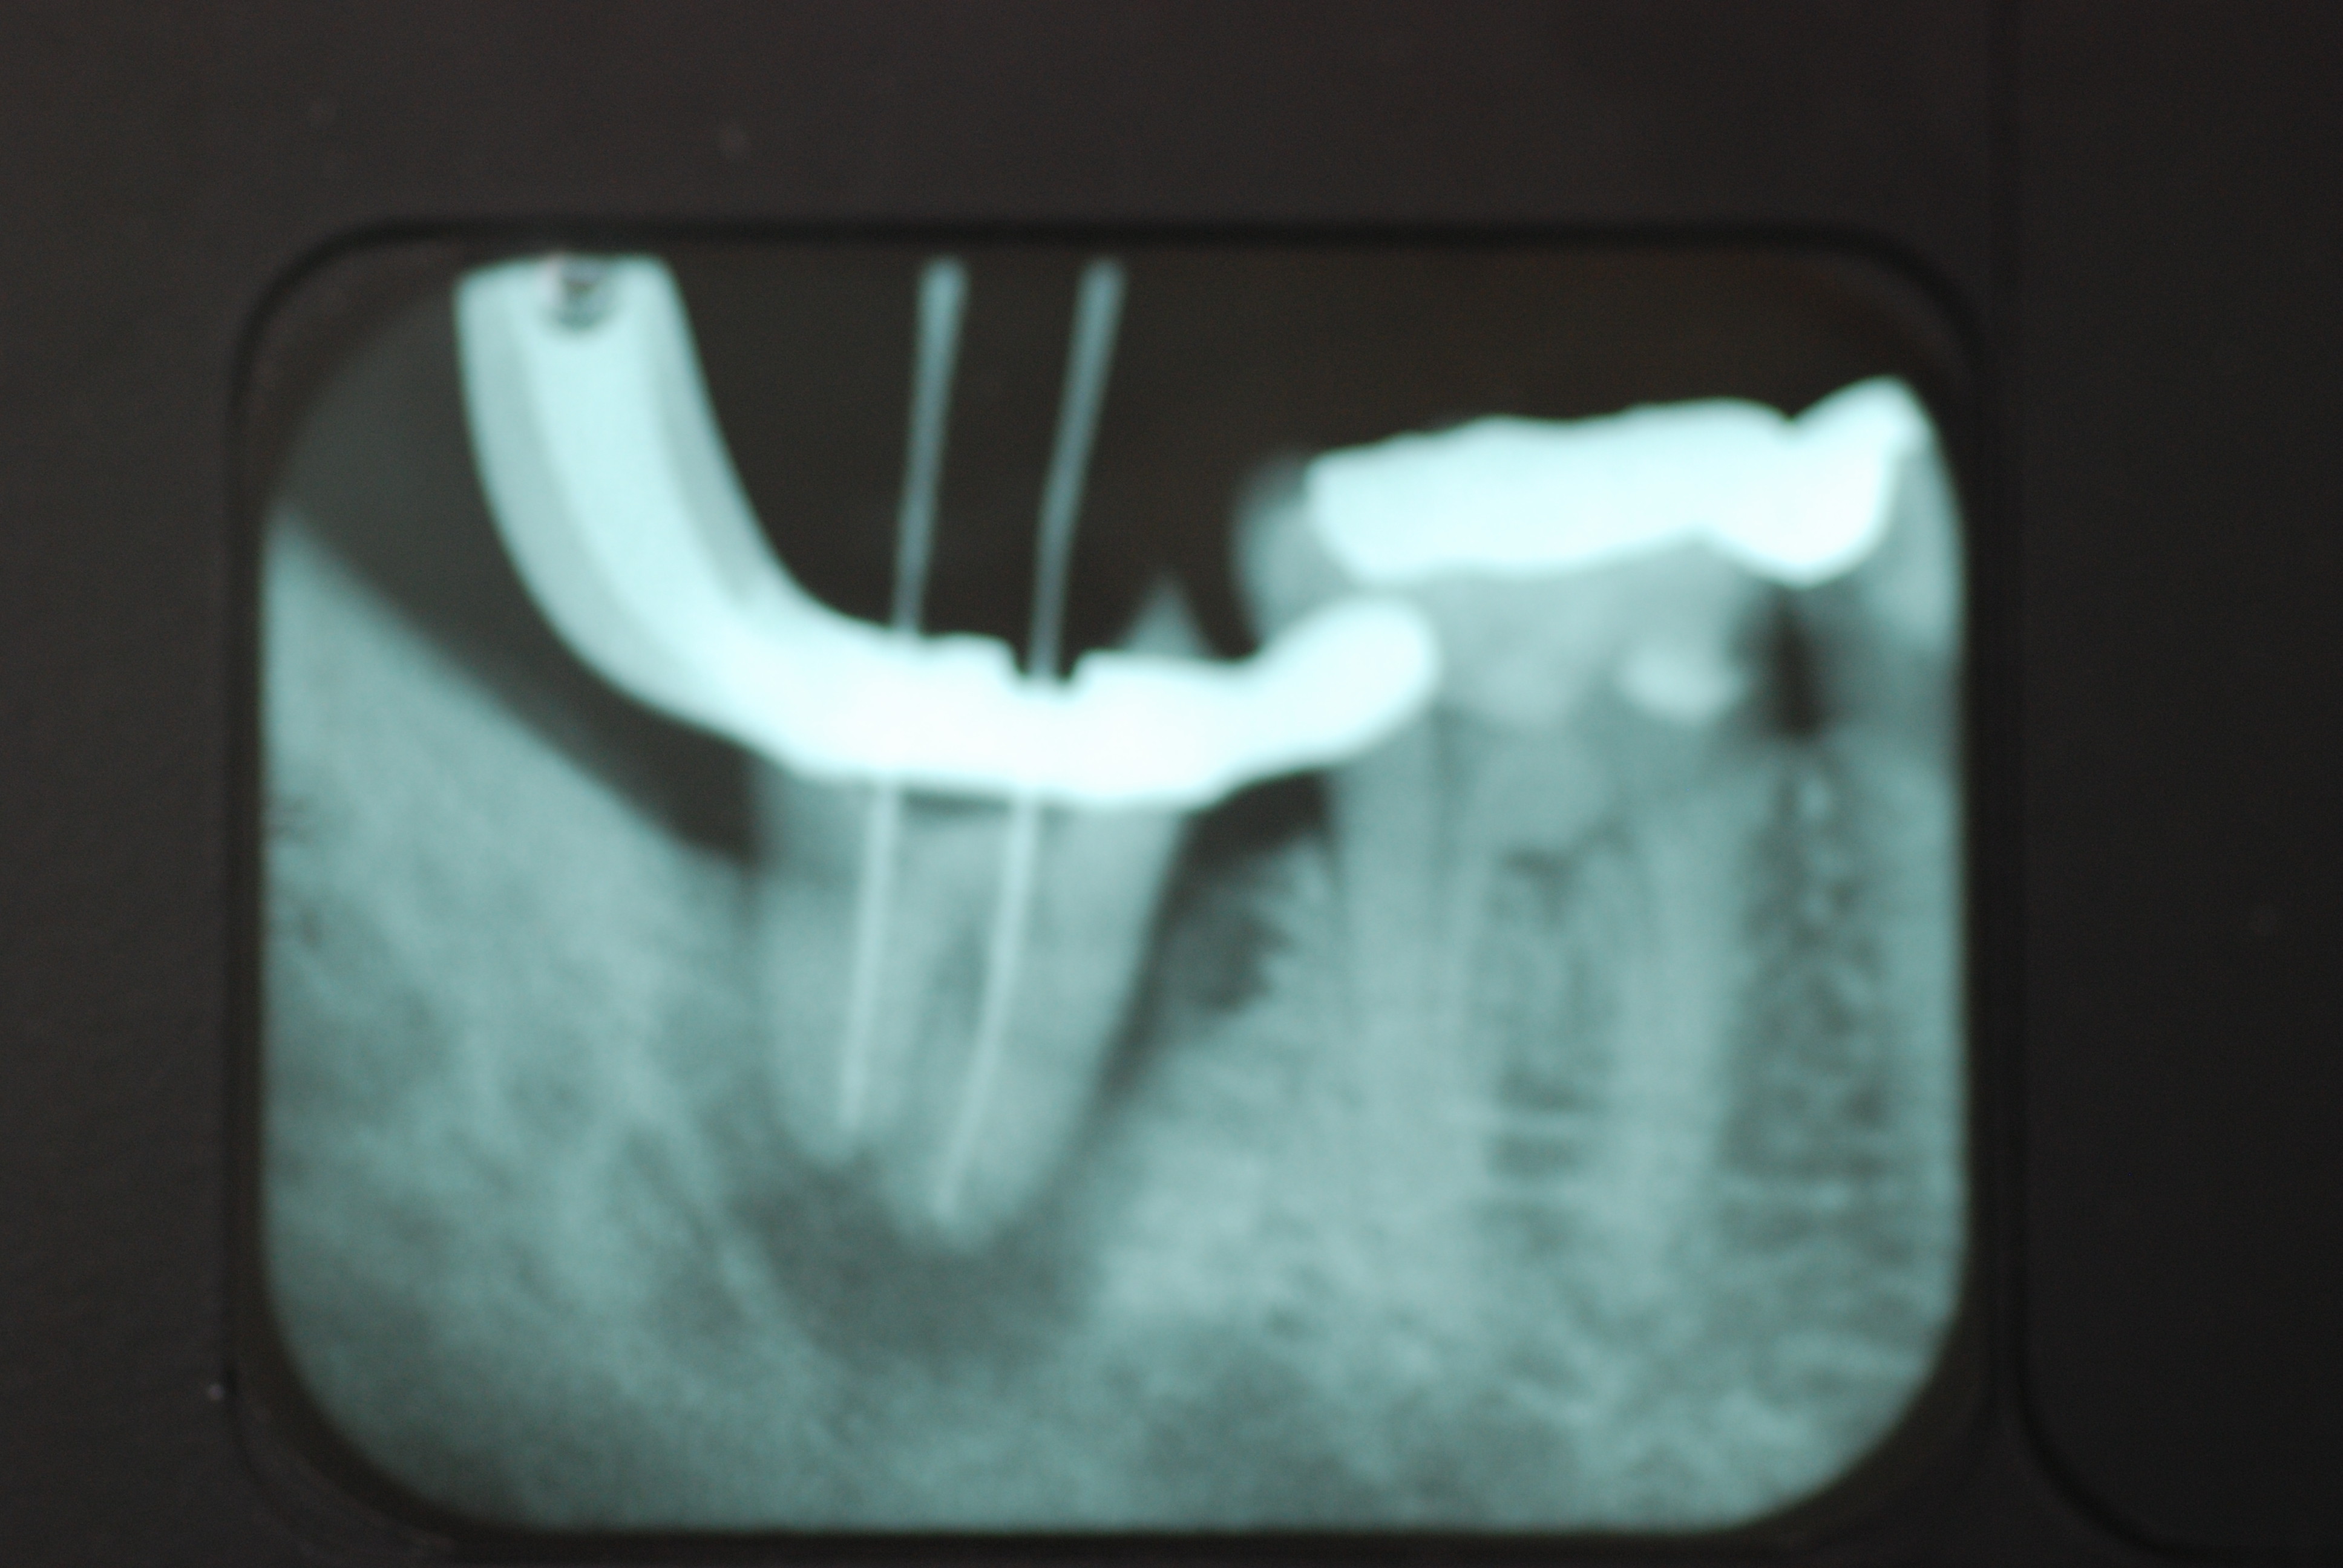

左下の一番奥の歯の治療がいい加減なようです。

そして歯周病を併発していて別の歯科医院で抜くしかないと言われて何とかならないかと当院に来られました。

左下の一番奥の歯の治療がいい加減なようです。しかし治療をしてみると滅菌しながら治療をすることの困難さを痛感しました。

三本ある根管の内、難しい手前の根幹の治療が為されていません。顎の骨に黒い影ができています。

根管治療終了です。

骨の部分は健康を回復しています。影がありません。治療が成功しています。